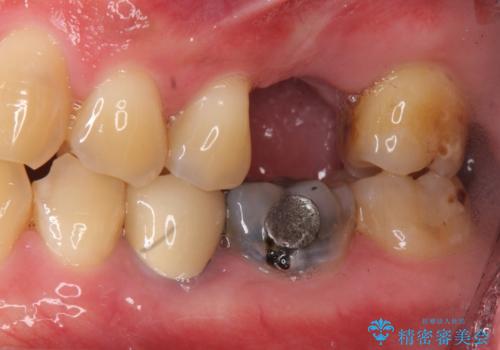

[入れ歯にしたくない] 臼歯部インプラント補綴